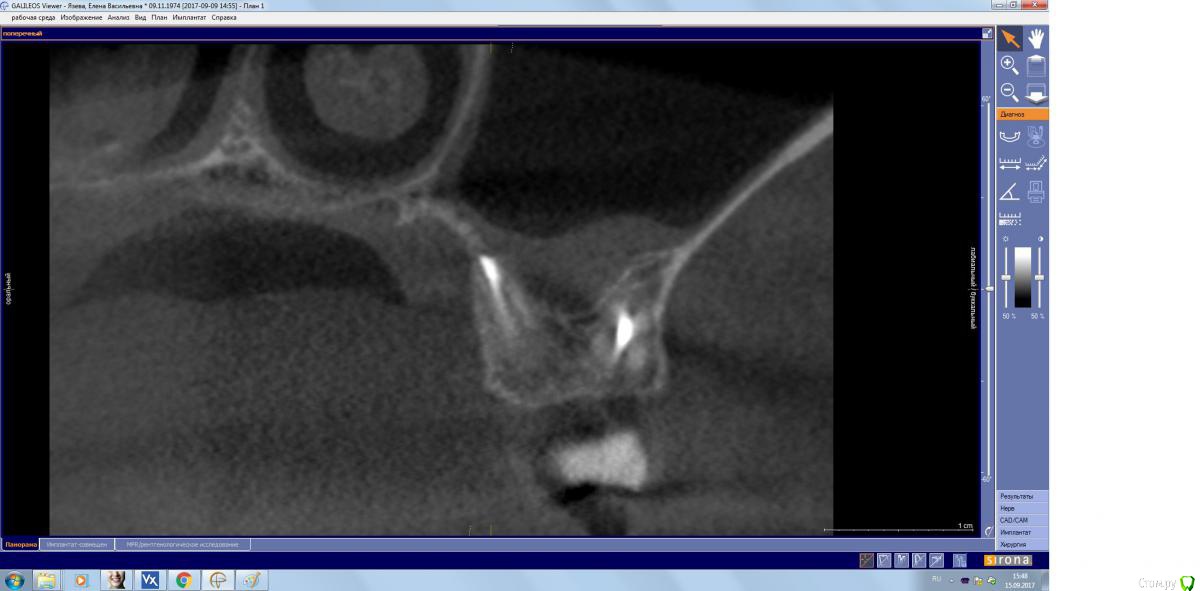

kamranchick Опубликовано 15 сентября, 2017 Поделиться Опубликовано 15 сентября, 2017 Господа, терапевт наш пролечил зуб, и болит пазуха уже месяц... сам зуб не болит, какой план действий? Ссылка на комментарий

kamranchick Опубликовано 15 сентября, 2017 Автор Поделиться Опубликовано 15 сентября, 2017 (изменено) Лор говорит хронический гайморит в стадии обострения, но провоцирует зуб, короче все как всегда... Изменено 15 сентября, 2017 пользователем kamranchick Ссылка на комментарий

parallax Опубликовано 16 сентября, 2017 Поделиться Опубликовано 16 сентября, 2017 Это пристеночно-гиперпластическая форма гайморита, застарелая хронь, которая появилась не вчера. Возможно, обострение спровоцировали паффы (куда ж без них). Я думаю, стоматологи тут не при чём. Хотя ЛОРики всегда обвиняют нас (скоро вменят убийство Кеннеди). В каналы лезть больше не надо, отправляйте в ЛОР отделение, лечение этого гайморита хирургическое. 1 Ссылка на комментарий

ger_berra Опубликовано 2 октября, 2017 Поделиться Опубликовано 2 октября, 2017 Решётчатый лабиринт посмотрите. Там часто много чертей сидит. Ссылка на комментарий